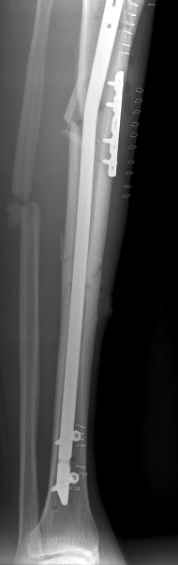

1

2

These can be challenging. I agree w/ all Dr. Carr's points. My preference to prevent the deformity is to use an anteromedial plate. See attached case.